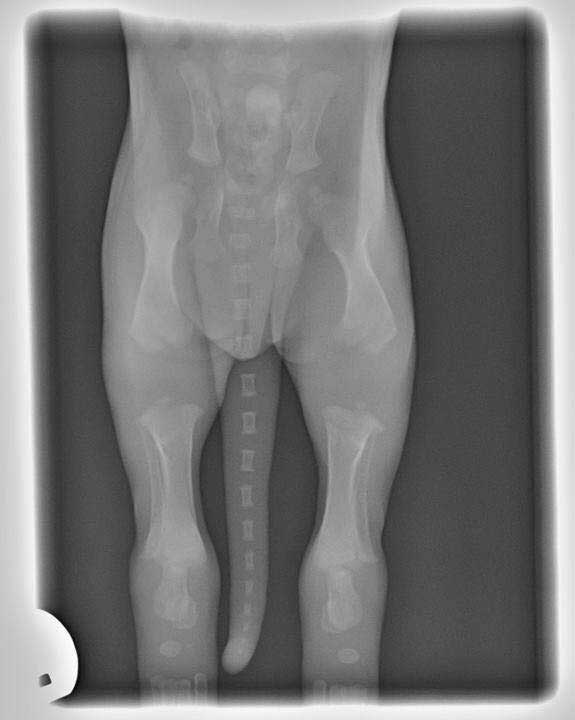

3. GROWTH PLATES

Growth Plates

Young puppy. Long way to go before the growth plates close. Be careful.